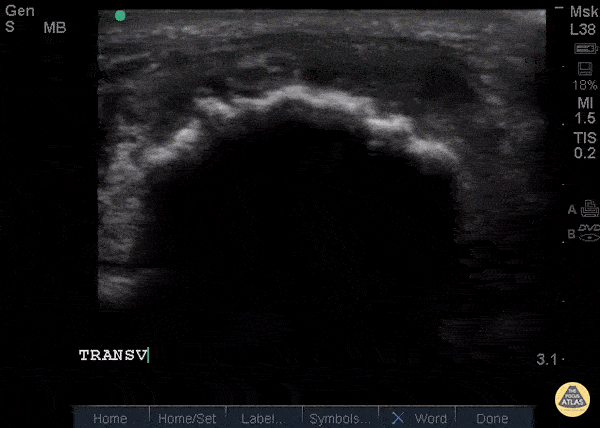

Musculoskeletal - Patellar Tendon Rupture Transverse

34 y/o M presented with swelling and pain inferior to his knee following hearing a pop when he jumped playing basketball. Pt unable to extend leg and x-ray demonstrated a high riding patella. Longitudinal ultrasound showed a hyperechoic tendon that is not continuous between the patella and tibia, with an anechoic area of hemorrhage consistent with patellar tendon rupture. Patellar tendon rupture can be diagnosed with H&P and POCUS can be used to confirm this diagnosis. In one study, diagnosis of tendon rupture by physical exam had a sensitivity of 100% and specificity of 76%, while diagnosis by POCUS had a sensitivity of 100% and specificity of 95%. Ultrasound is especially useful in patients who cannot cooperate with a physical exam, and serial ultrasound can also be used to monitor healing of a tendon rupture. Caroline Rago - MS4, Dr’s Bryan Jarrett and Joshua Schechter - Kings County Emergency Medicine